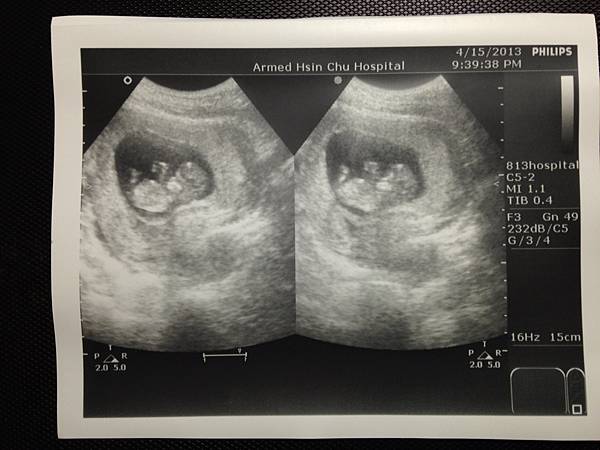

(這是果然有小朋友的樣子了耶)

你現在有4.67cm嚕

心跳164下, 大約是11週3天

可是個有頭有臉的小傢伙, 還看得到你的雙腳呢!

(小腳丫併在一起的感覺好可愛呦!)